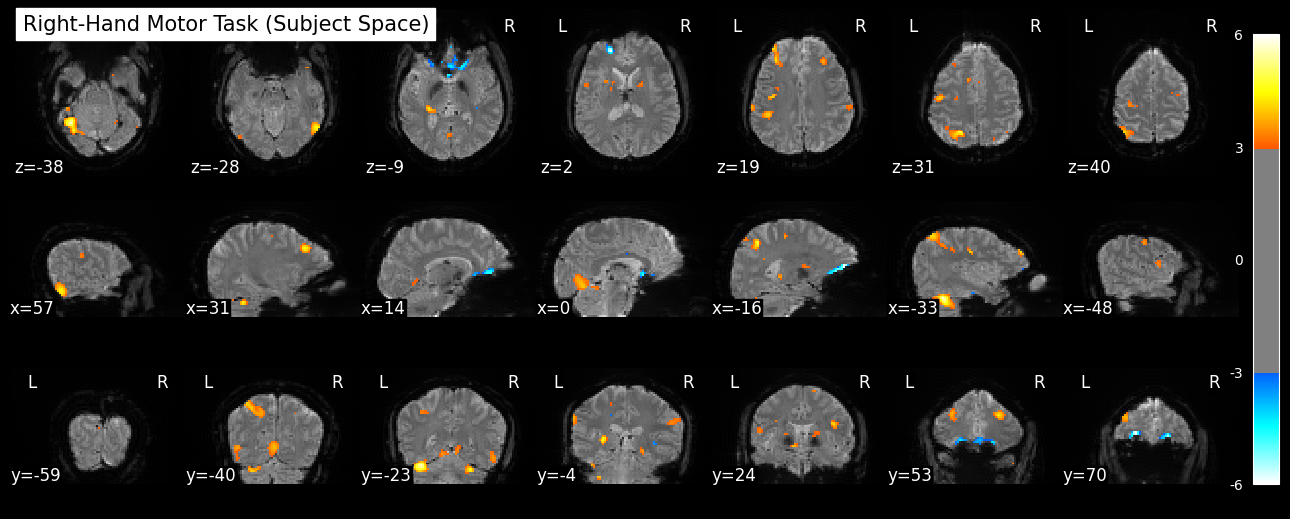

a quick look at my fmri

Whats going on here ? 🤔